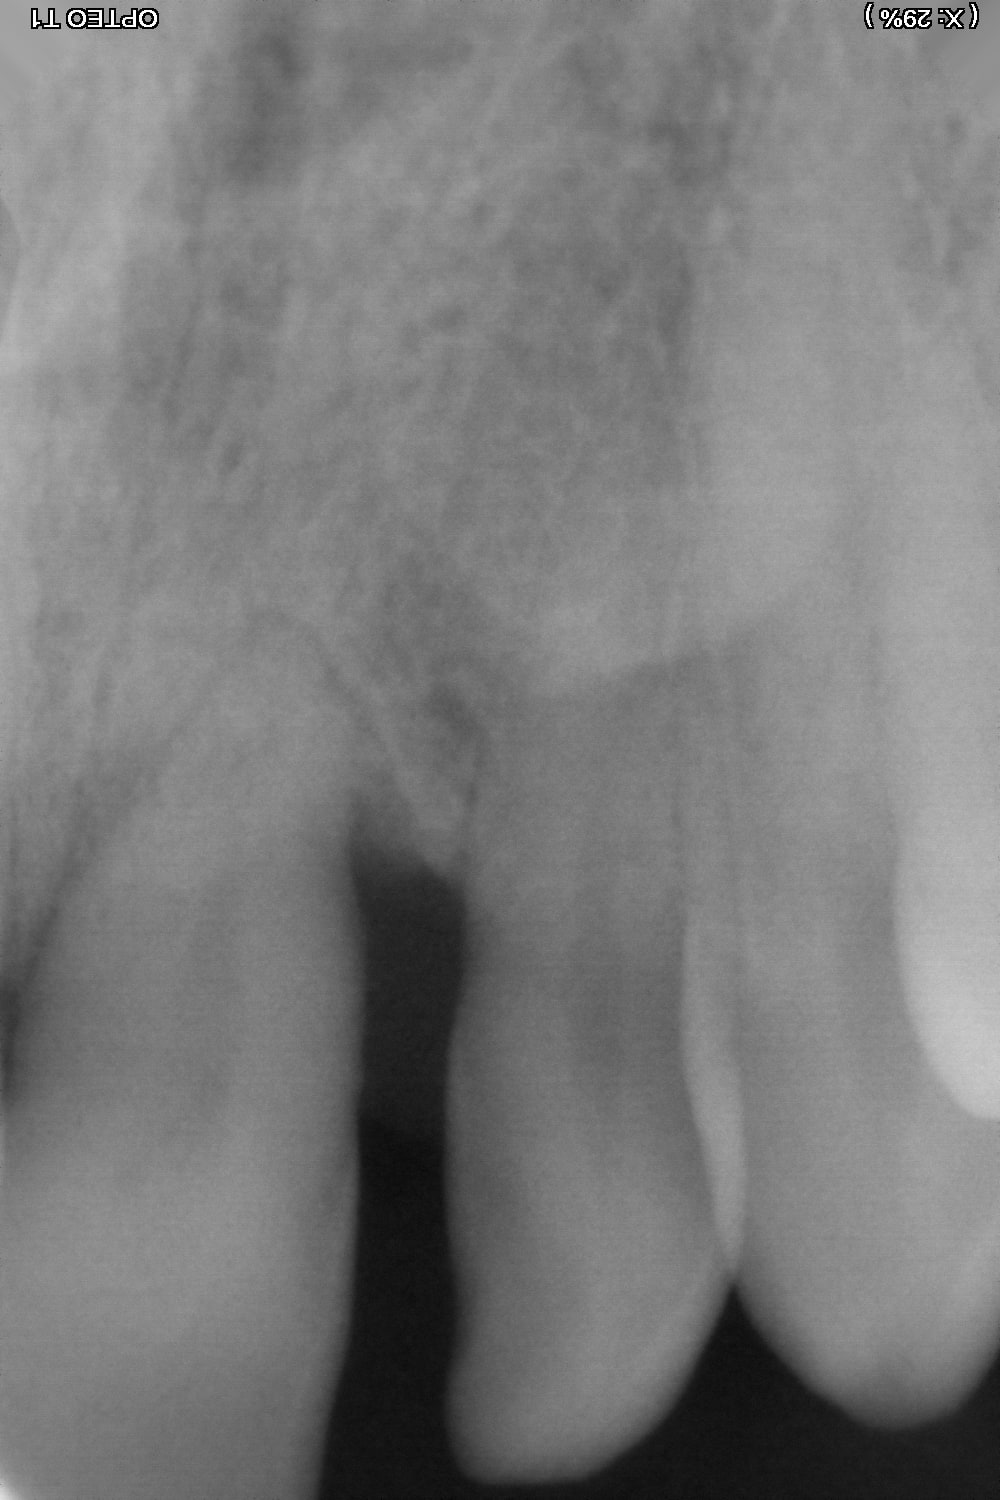

Que proposeriez vous à cette patiente de 40 ans dont la 21 s'est égressée...

Je la vois pour la 1ere fois, le sondage parodontal ne montre pas de poche parodontale (un long epithelium de jonction?)

pas de poche????

t'as vu la tronche de cette 21???

la courbe de Spee est prononcée, les incisives inf paraissent égressées et vestibulées, l'onde de choc masticatoire arrive à 90° sur les inc sup, la langue est ptêt basse. je commencerais par niveler et redresser les inc inf pour libérer les inc sup de toute la charge occlusale, puis rétablissement du guide incisif en redressant les inc sup

ce qui s est passé mr les jurés , ç est que l on se retrouve face à un DAM d origine musculaire causé par une interférence postérieure unilaterale au plus pres de l axe charniere .

autrement dit le cas type de la diagonale de Thielemann. comme évoqué par Dancha .

la nuit , lorsque la gonzesse dort ,pour éviter sa prématurité elle serre fort sur 21 / 22 avec la mâchoire du bas de traviol , en ciseau , quoi .